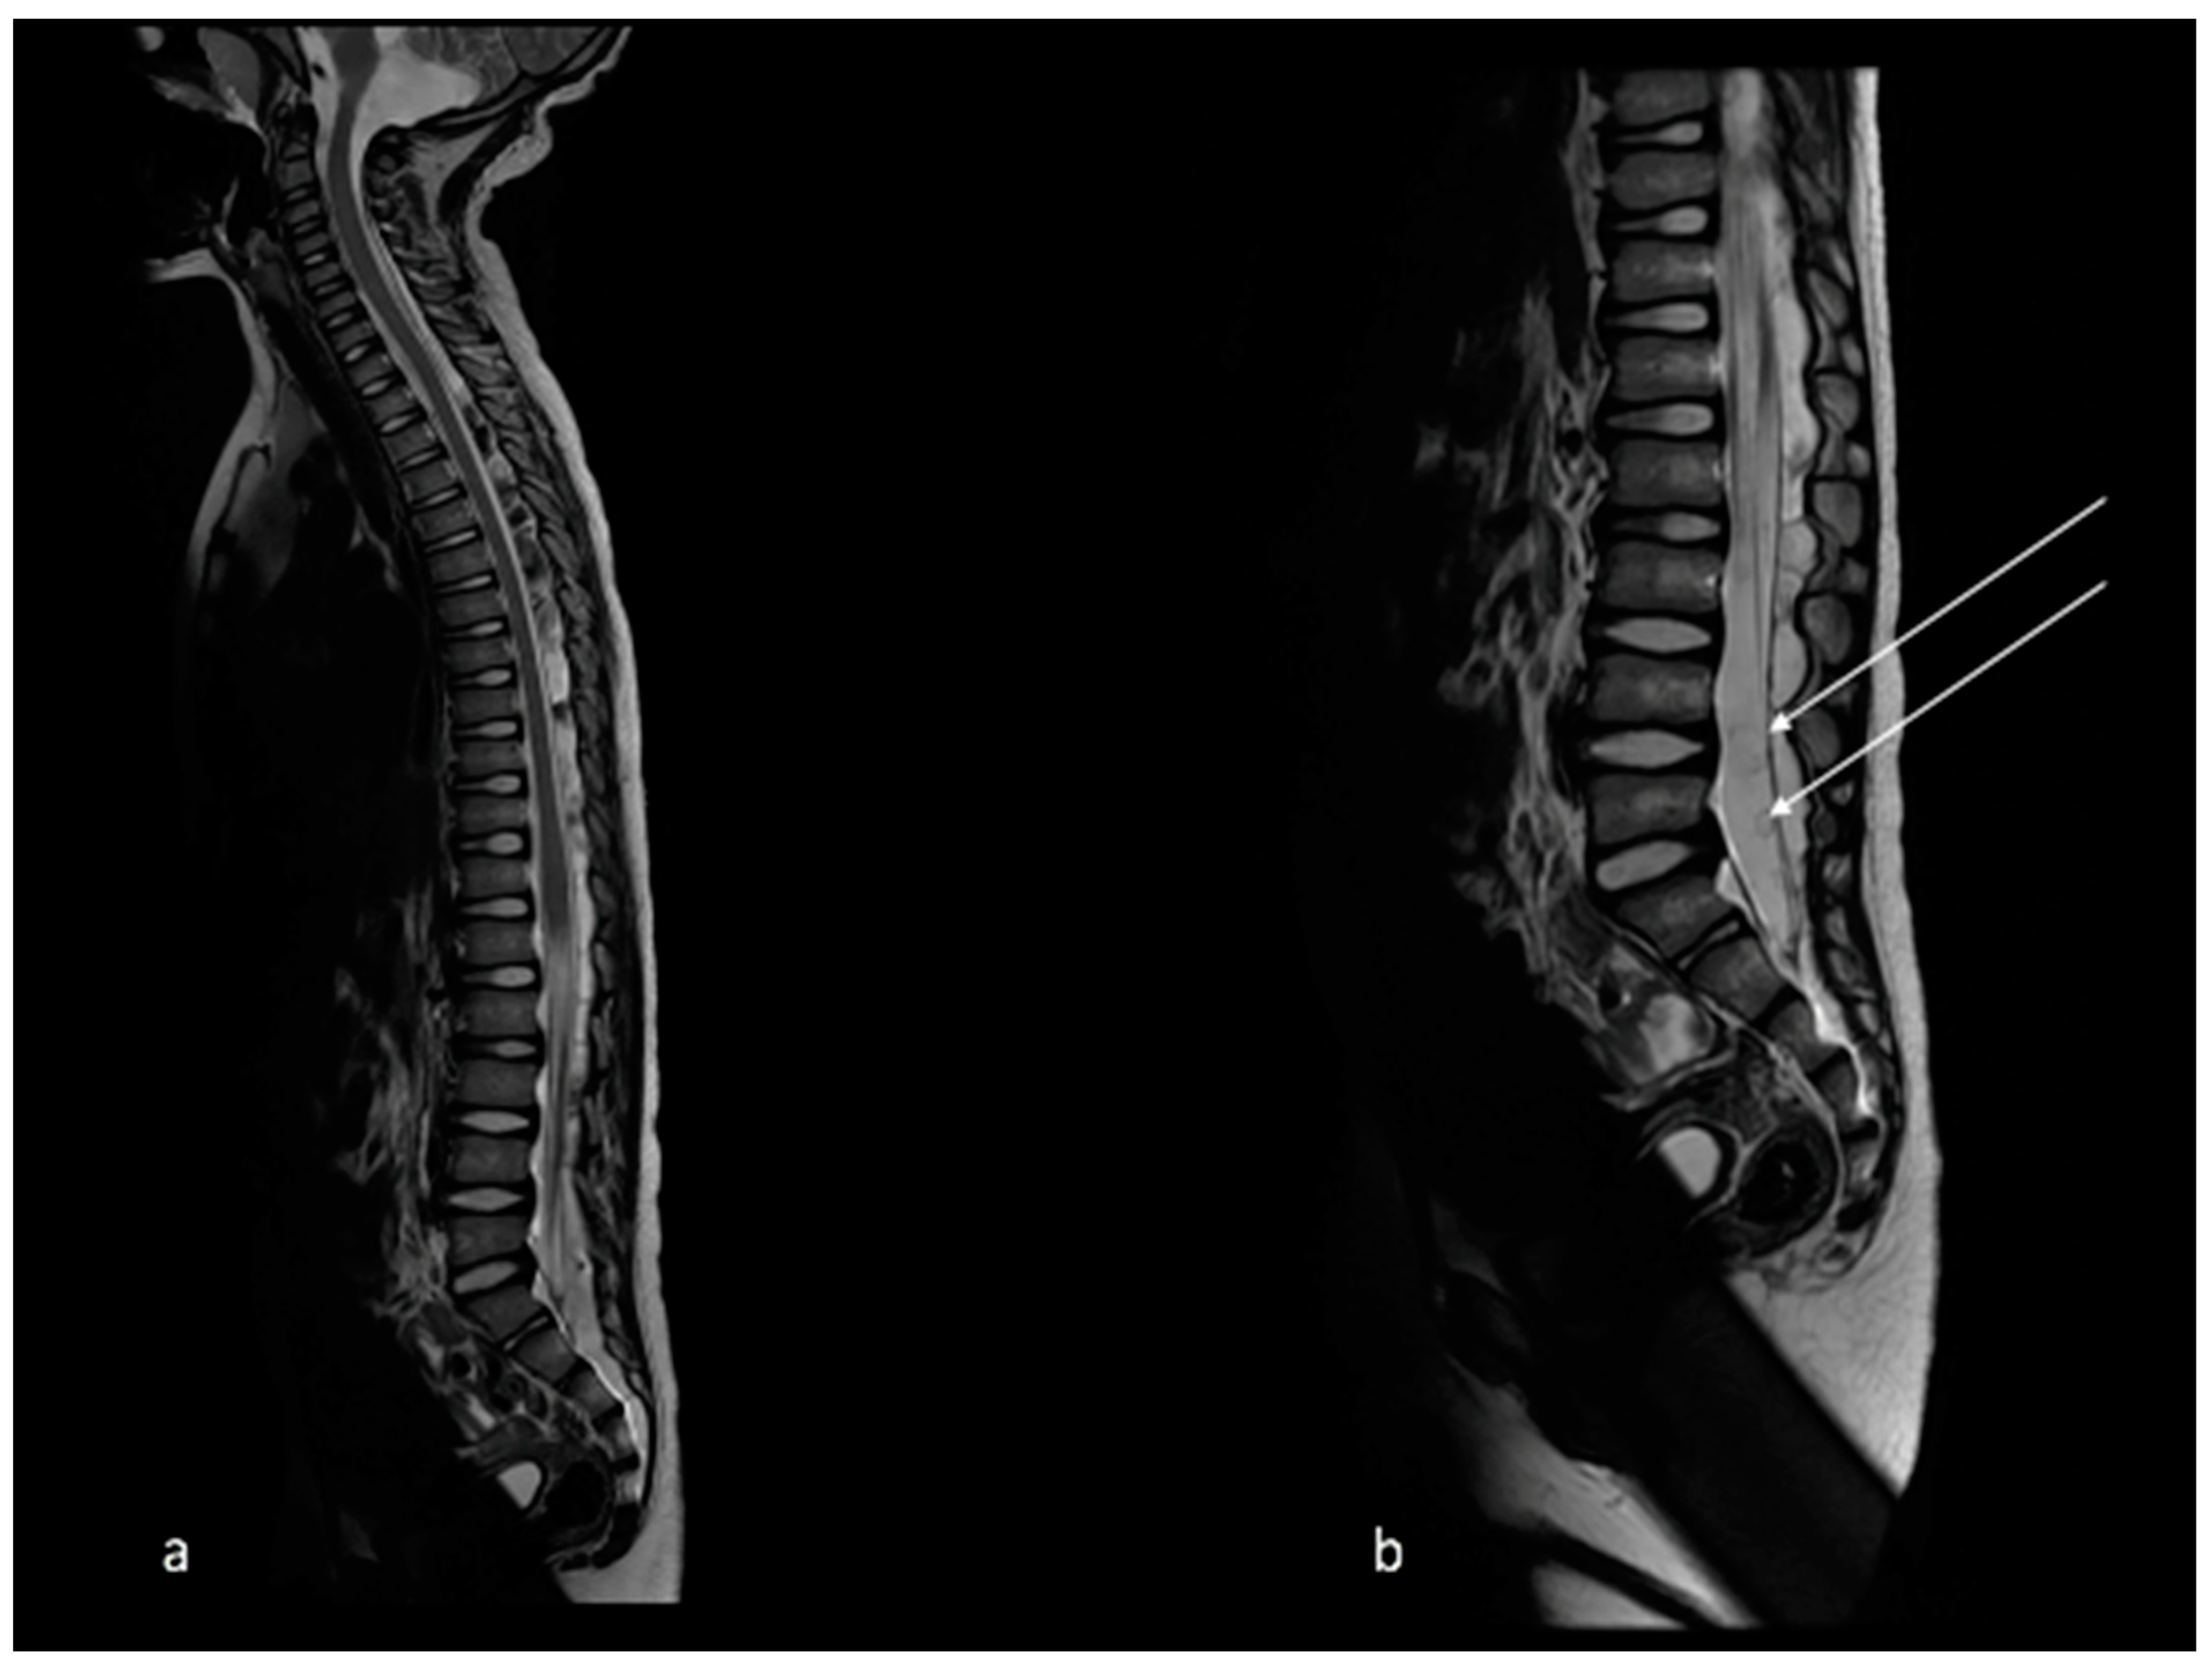

2. Case Report